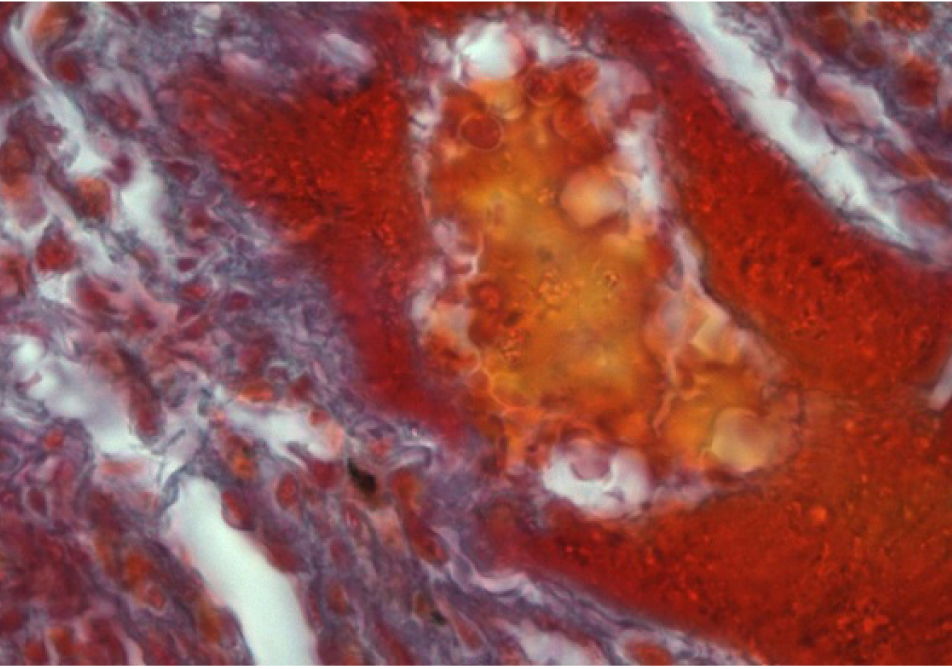

При исследовании гистологических срезов в легких определяются безвоздушные участки, чередующиеся с эмфизематозно расширенными (рис. 1).

Рис. 1. Безвоздушные участки легкого, чередующиеся с эмфизематозно измененными. Окраска гематоксилином и эозином. Ок. 10. Об. 4